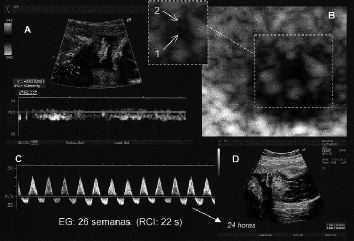

En resumen, antes de las 18 semanas el feto presenta una midriasis basal, y tras el estímulo DC responde con una miosis; después de la semana 19, alcanza una miosis basal y responde con una midriasis tras el estímulo Doppler color (Figs. 8 y 9).

Figura 8. Fotograma A: miosis basal en la semana 29. Fotograma B: midriasis tras el estímulo DC. 1 = Párpado superior. 2 = Pupila. 3 = Iris.

Figura 9. 31 semanas. Fotograma A: miosis basal. Fotograma B: midriasis post DC. 1 = Pupila. 2 = Iris.